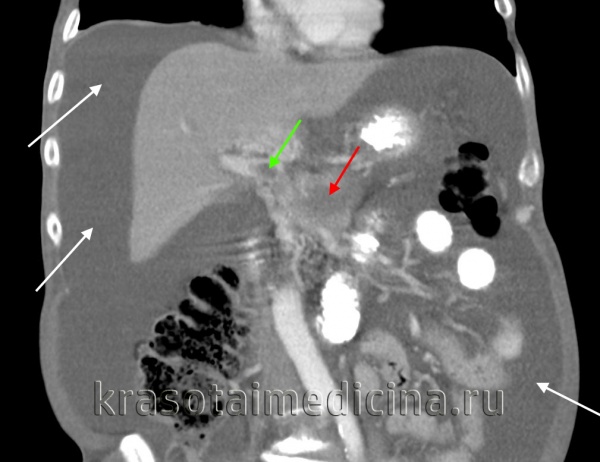

КТ ОБП. Портальная гипертензия на фоне обструкции воротной вены опухолью поджелудочной железы (красная стрелка). Опухолевый тромб (зеленая стрелка) в воротной вене. Асцит (белая стрелка).

КТ ОБП. Этот же пациент, расширенный левый долевой ствол воротной вены (синяя стрелка) с периваскулярным отеком (желтая стрелка).

КТ ОБП. Этот же пациент, варикозно расширенные вены как проявление синдрома портальной гипертензии (коричневая стрелка).